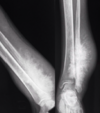

¿Cómo se ve el codo de tenista/golfista en Rx?

Si hay calcificación significa que es:

A

Aumento densidad y volumen en epicóndilo medial o lateral

Calcificación –> crónico